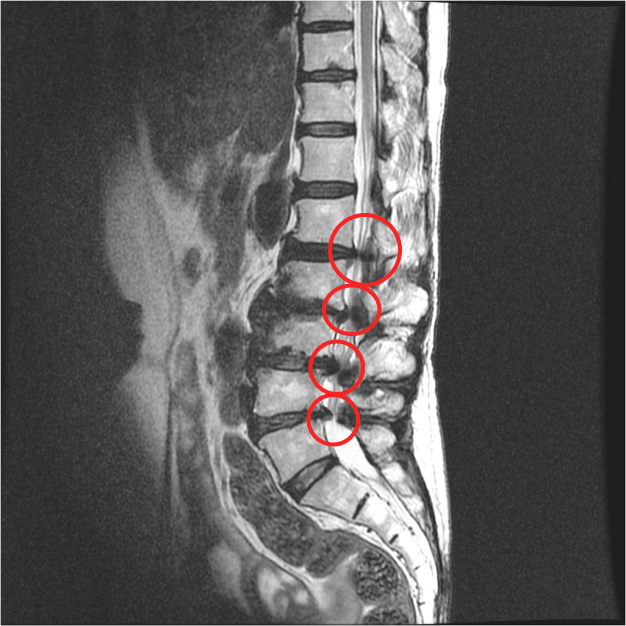

② 척추관 협착증

30대 이후부터 척추의 퇴행성 변화가 시작되면서 척추 뼈 사이 공간이 점차 좁아지는 질환입니다. 뼈의 퇴행으로 인해 골극(가시 같은 모양으로 튀어나온 뼈)이 생기고, 주변 인대가 두꺼워져 척추관이 4방향에서 압박됩니다. 결과적으로 척수와 신경근이 눌리면서 다리 저림, 당기는 증상, 장거리 보행 시 통증이 나타납니다.

- 허리+엉덩이+다리 저림 및 감각 이상: 허리디스크, 척추관 협착증 등 신경 압박이 심한 질환. 허리에서 다리 바깥쪽, 발등까지 통증이 이어질 수 있음